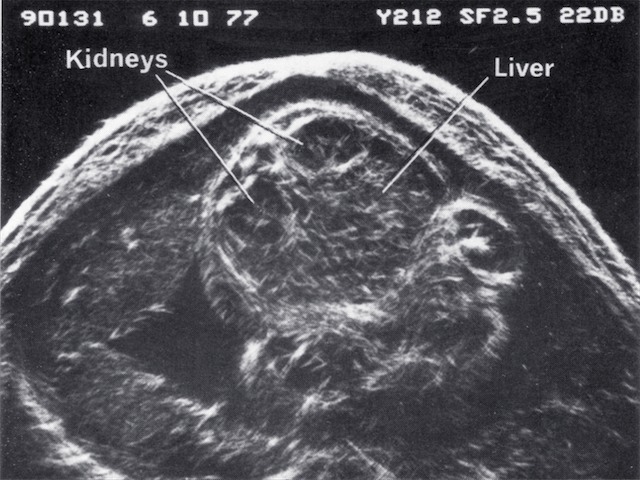

| 1968 | Demonstration of fetal orbits, heart, bladder, kidneys and scrotum |

| 1970 | Introduction of grey scale ultrasound, improving dramatically the demonstration of normal and abnormal structures in the fetus, placenta and mother |

| 1980 | Demonstration of fetal lung, liver and bowel maturation by grey scale ultrasound |

- Fetal kidney and liver 1969